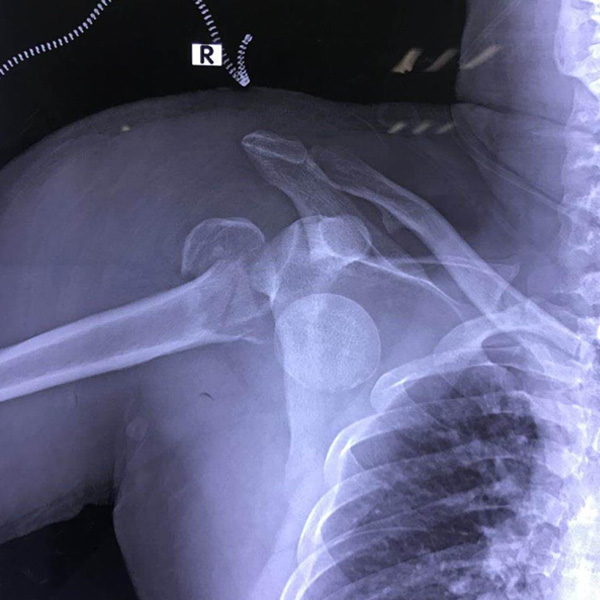

右側肱骨頭置換

患者郭某,男,40歲,因嚴重車禍導致“右肱骨頭粉碎性骨折”,一般的手術很難將粉碎的骨折塊拼接起來,即便大致的拼接起來,因為骨面的不平......